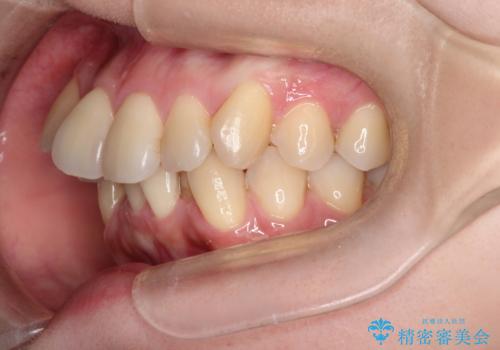

ガタガタの抜歯矯正を裏側ワイヤーを使っての目立たない矯正

- 八重歯とガタガタを主訴に来院されました。

目立たないワイヤー矯正を希望されたので、上下左右のはを1本ずつ抜歯して、ハーフリンガル(上顎だけ裏側)にて矯正をすることにしました。